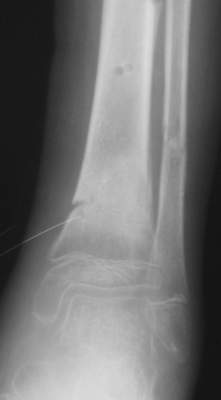

Нашел в комп-ре схожий случай:

1) з/репозиция, 2) фиксация 2 спицами, 3) аппарат, 4) фиксационные

спицы удалены...

См. аттачт.

А можно было наложить аппарат и по поводу ложного сустава...

По крайней мере не было бы укорочения (пусть и в 2 см)...